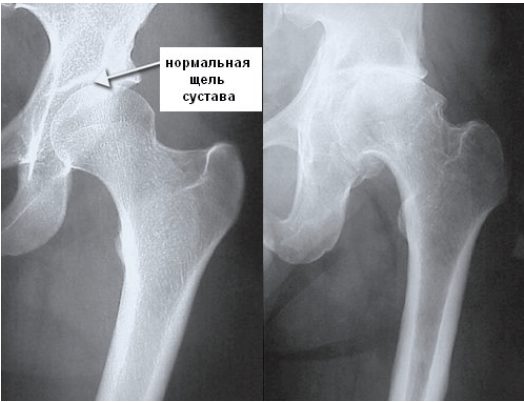

- сужение суставной щели. Признак дистрофических изменений суставных хрящей. Этот симптом выявляют у больных с деформирующим остеоартрозом и хроническими артритами;

Деформирующий остеоартроз. На ранних стадиях рентгенологические признаки отсутствуют. Позже о патологии говорит сужение суставной щели.